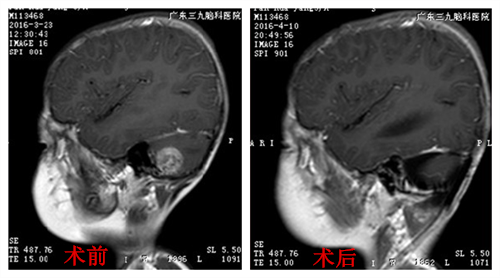

一个月前,晖晖又出现间断性头痛、恶心呕吐,家人意识到有可能是肿瘤复发,于是带着晖晖前往广州的广东三九脑科医院。晖晖头颅磁共振检查显示,右侧桥小脑角区及上段脊髓右旁、四脑室内多发病灶并强化灶,考虑:右侧桥小脑角区及上段脊髓右旁、四脑室内室管膜瘤。据小儿神经外科专家介绍,室管膜瘤属于中枢神经系统肿瘤,好发于儿童及青年,首选治疗方案为外科手术,不过该肿瘤术后复发率较高,多数为瘤床原位复发,对于肿瘤生长部位深、难以做到瘤体全切者,次全切除亦可获得良好的治疗效果。

完善术前相关检查,无手术禁忌症,小儿神经外科在全麻下为晖晖进行肿瘤切除术,手术顺利。术后病理:室管膜瘤 (WHO II级)。